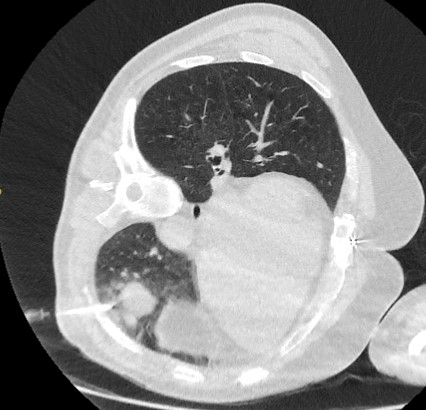

Computed tomography (CT) showing a right upper lobe posterior cavitating nodule, with biopsy confirming granulomatosis with polyangiitis

From the collection of Dr George Tsaknis, MD, PhD, FRCP(London), MRQA, MAcadMEd, PGCert; used with permission